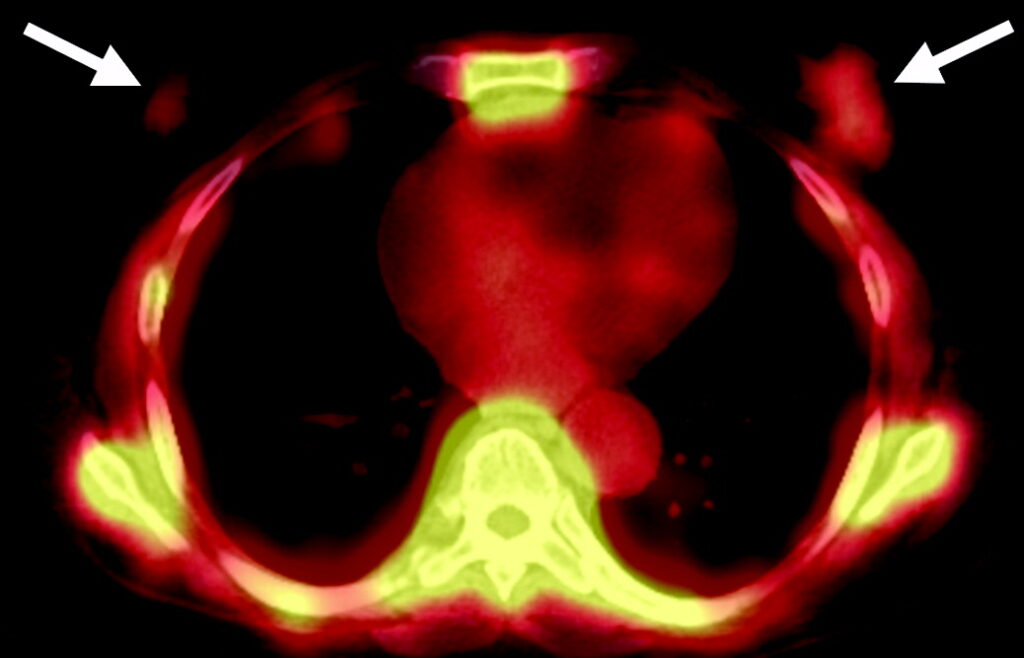

Uomo di 75 anni con tumore alla prostata.

L’immagine planare whole-body in proiezione anteriore della scintigrafia ossea mostra due foci di captazione nella parte inferiore del torace (frecce), sovrapposti alle coste anteriori, inizialmente ritenuti localizzati nelle coste stesse.

L’acquisizione tomografica ibrida risolve definitivamente l’ambiguità spaziale creata dall’immagine planare. Le fette assiali dimostrano che i due focolai di ipercaptazione risiedono nei tessuti molli superficiali sovrastanti le coste, localizzandosi esattamente nel tessuto mammario retroareolare bilaterale.

La captazione simmetrica a livello mammario in un paziente di sesso maschile trattato per neoplasia prostatica è indicativa di ginecomastia indotta da farmaci. L’ipertrofia benigna della ghiandola (che capta il radiotracciante in via extra-ossea) è un ben noto effetto collaterale della terapia di deprivazione androgenica (o della terapia estrogenica).